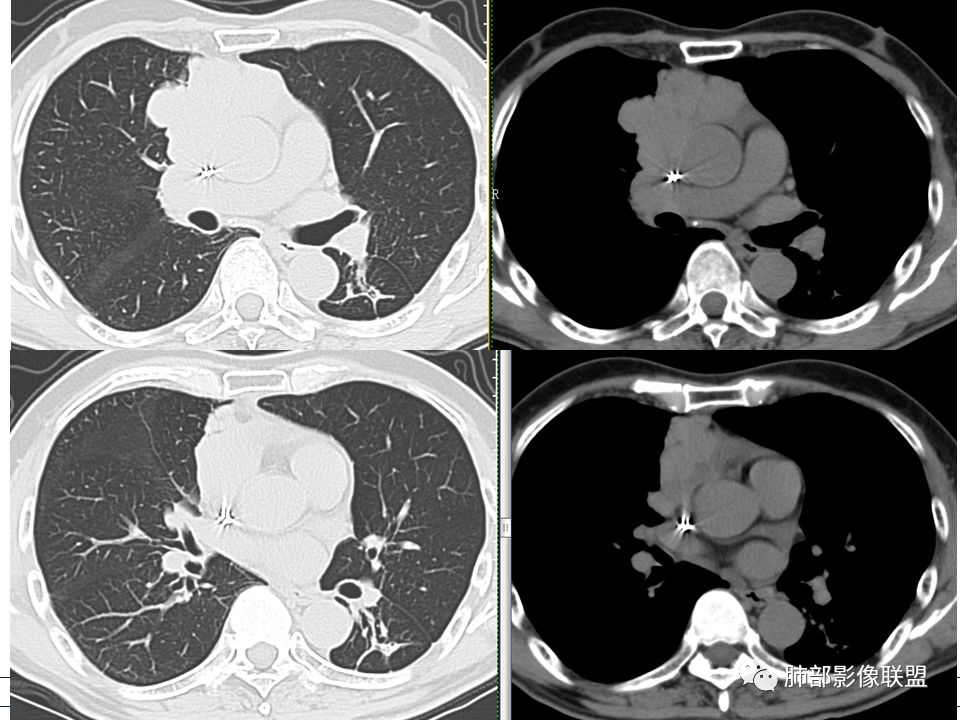

南边: 支持点:主体在纵隔、与肺分界清楚,与支气管、肺血管关系不密切

琦遇: 病灶与大血管脂肪间隙消失,也是提示不在肺内

南边: 从病灶与血管的关系看,骑跨在主动脉上,上腔静脉后移,病灶整体前朝后推,但是跨中线到对侧,主动脉偏移不明显,提示病灶前方来源,朝后推,如果侧方来源,朝对侧推移,支持前纵隔来源,然后就是性质?性质一般两个方向,有些有特征性征象,直接定病理可能比定良恶性更容易;有些特征性正想没有,但是可以提示良恶性,前纵隔肿瘤:胸腺、淋巴、(这年龄生殖类不太支持)

琦遇: 有分叶、有钙化、无坏死、有明显强化,不规则分叶,脂肪间隙模糊,与大血管分界不清,应该支持恶性多点吧,但是侵犯性不强

南边: 然后神经、脂肪,最多见的:胸腺的瘤、癌,其次淋巴瘤;然后才是其他,分叶明显,点状钙化,线样间隔,支持胸腺瘤吧,高度怀疑胸腺瘤